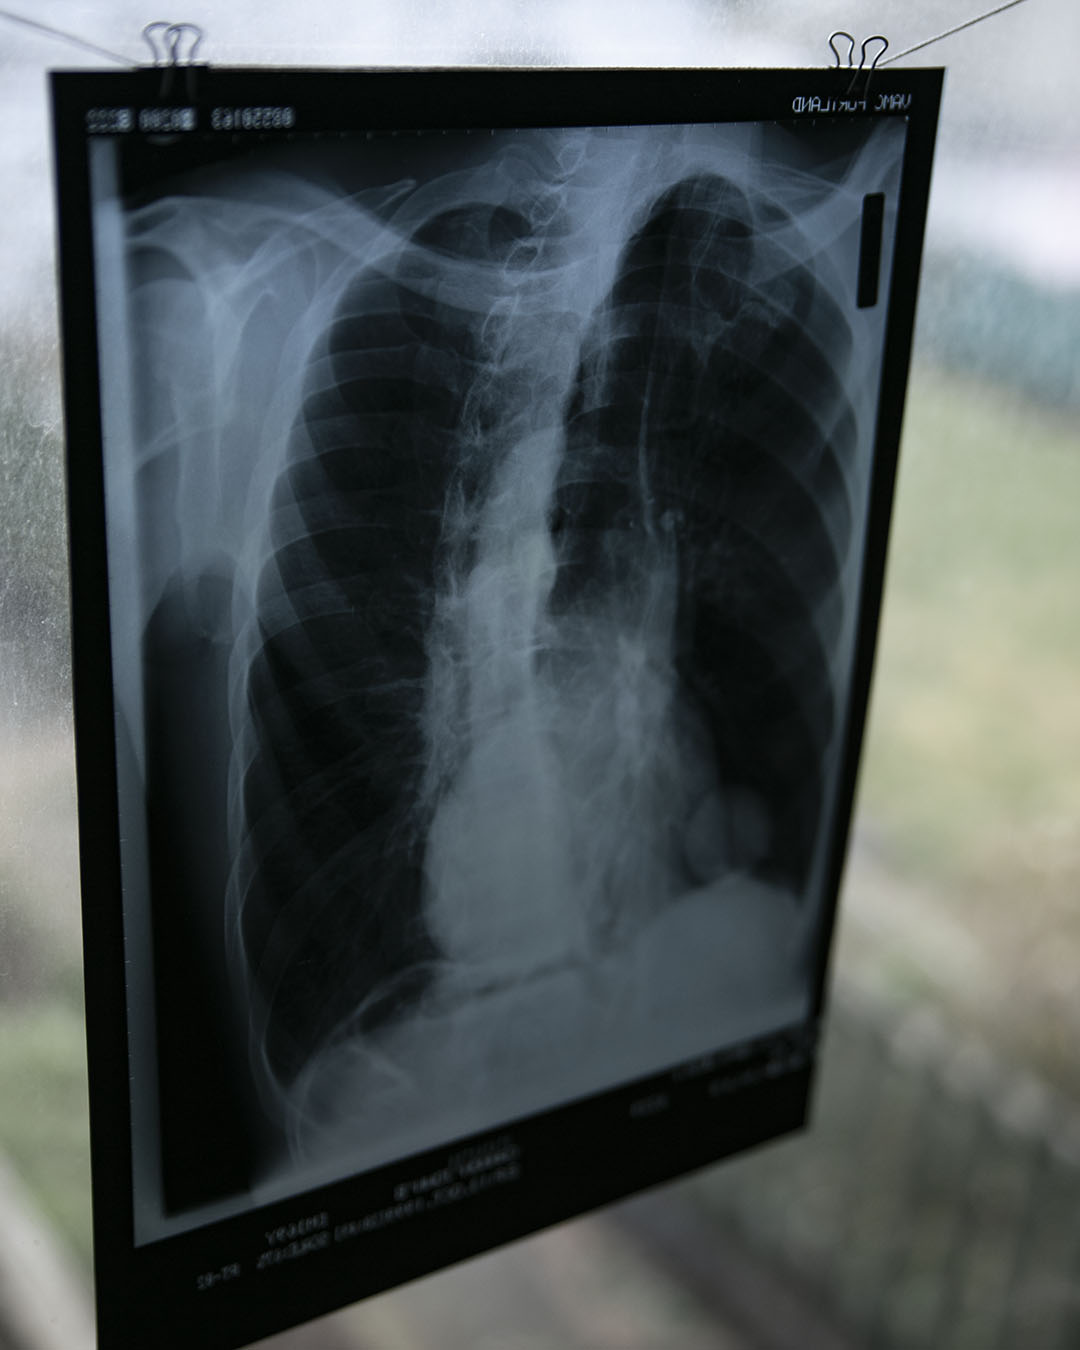

Vintage Chest X-Ray

Vintage Chest X-Ray

Amazing vintage x-rays, price is for one and the one you receive may differ from the examples photographed. There is about 20 available, sourced from the US. All unique and in good condition. Approx 35x28cm